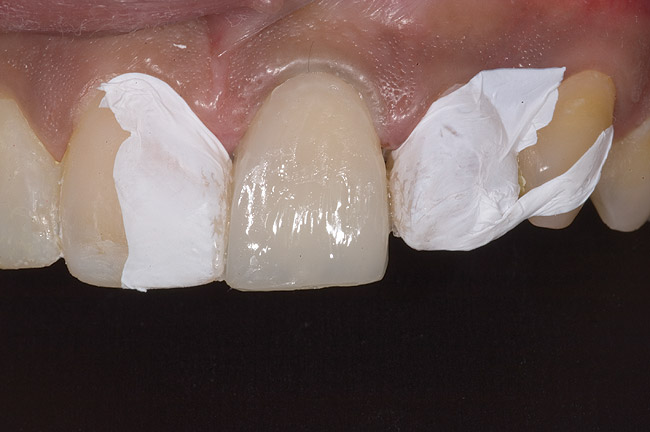

Figure 10  Tooth No. 9 with no preparation on the palatal surface to restore lost form with bonding resin.

Figure 10

During the next appointment, a palatal index of the approved provisional was fabricated with putty silicone. This enabled the clinician to precisely build the lingual surfaces and incisal edges of teeth Nos. 6 through 11. The provisional mock-up resin on No. 9 was removed, and the underlying labial tooth was roughened with an abrasive diamond bur. No tooth structure was removed from the palatal surface, and unsupported enamel was rounded off from the labial. An ultrathin dry cord was placed in the gingival sulcus on No. 9 (Figure 9 and Figure 10). Teflon tape was used to isolate No. 9 from adjacent teeth. Then 37% phosphoric acid was used to totally etch the labial surface for 10 seconds and the palatal surfaces on No. 9 for 5 seconds. Single bond was applied and spread uniformly across the tooth and light-cured for 20 seconds.